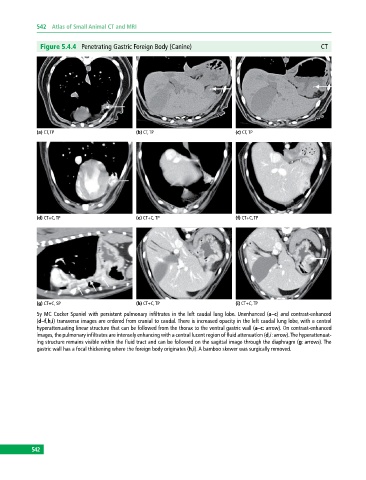

Figure 5.4.4 Penetrating Gastric Foreign Body (Canine) CT

(a) CT, TP (b) CT, TP (c) CT, TP

(d) CT+C, TP (e) CT+C, TP (f) CT+C, TP

(g) CT+C, SP (h) CT+C, TP (i) CT+C, TP

5y MC Cocker Spaniel with persistent pulmonary infiltrates in the left caudal lung lobe. Unenhanced (a–c) and contrast-enhanced

(d–f,h,i) transverse images are ordered from cranial to caudal. There is increased opacity in the left caudal lung lobe, with a central

hyperattenuating linear structure that can be followed from the thorax to the ventral gastric wall (a–c: arrow). On contrast‐enhanced

images, the pulmonary infiltrates are intensely enhancing with a central lucent region of fluid attenuation (d,i: arrow). The hyperattenuat-

ing structure remains visible within the fluid tract and can be followed on the sagittal image through the diaphragm (g: arrows). The

gastric wall has a focal thickening where the foreign body originates (h,i). A bamboo skewer was surgically removed.